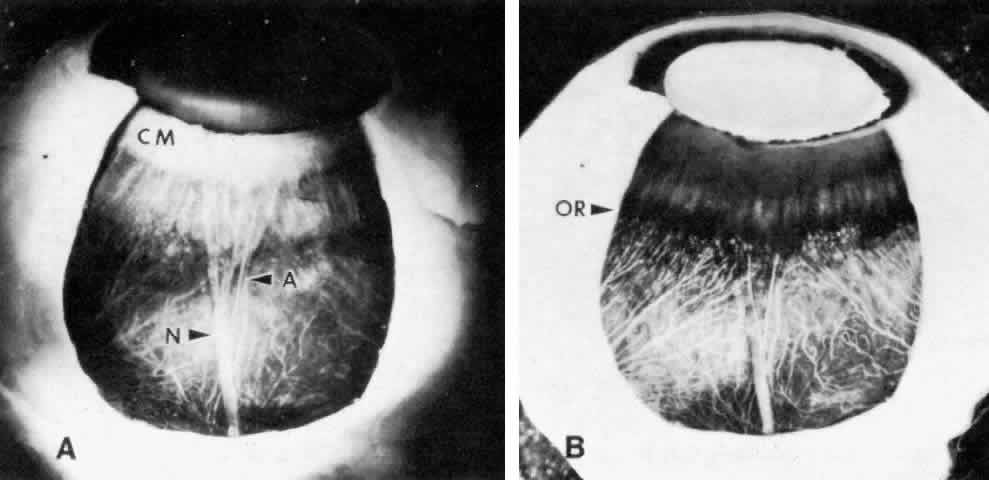

in traumatic hyphema. CILIARY MUSCLE The ciliary muscle has a complex architecture, and its three dimensional

organization and function have been difficult to visualize. Traditionally, the

muscle is divided into three portions (Fig. 34): an outer longitudinal or meridional portion ( Brücke's muscle), a

middle oblique portion (also called reticular or radial), and

an inner circular component ( Müller's muscle). These regions

are so interconnected that they were recognized early as designed to

function like a single muscle mass when stimulated.37 Experimental evidence in humans, primates, and other mammals supports

the view that the contracting ciliary muscle undergoes a shortening with

anterior traction on the ora serrata region, and an inward and posterior

pull on the scleral spur and trabeculum.6,38–40 Contraction of the oblique and circular portions in particular contributes

a strong anterior and inward movement of the processes. The result

is a well coordinated anterior-inward squeezing effect, displacing the

processes toward the lens equator, and resulting in relaxation of zonular

pull on the lens capsule. This inward movement of the ciliary processes

has been dramatically shown by cinematography in primates after

iridectomy.41  Fig. 34. Ciliary muscle showing circular (C), radial (R), and longitudinal (L) divisions

Several investigators have used somewhat different schemata based on muscle

dissection to illustrate the ciliary muscle fiber topography that

allows such a complex yet coordinated muscle movement. The muscle fibers

are visualized as each arising by two heads in interdigitating V patterns (Fig. 35).37,42,43 The two heads are close together in the longitudinal muscle so the fibers

pass in an almost straight anteroposterior direction. For the oblique

muscle fibers, the angle between the two heads is wider and for the

circular muscle fibers is obtuse, allowing the latter to function in

an almost purely circular plane.  Fig. 35. Diagram of ciliary muscle divisions: circular (C), radial (R), and longitudinal (L). Anterior

attachments to the collagenous scleral spur (SP) and

the trabecular beams are indicated. SC, Schlemm's canal. (Modified from Hogan MJ, Alvarado JA, Weddell JE: Histology of the Human

Eye. Philadelphia, WB Saunders, 1971; and Rohen JW: Der Ziliarkorper

als functionelles System. Morph Jahrbuch 92:415, 1952) Fig. 35. Diagram of ciliary muscle divisions: circular (C), radial (R), and longitudinal (L). Anterior

attachments to the collagenous scleral spur (SP) and

the trabecular beams are indicated. SC, Schlemm's canal. (Modified from Hogan MJ, Alvarado JA, Weddell JE: Histology of the Human

Eye. Philadelphia, WB Saunders, 1971; and Rohen JW: Der Ziliarkorper

als functionelles System. Morph Jahrbuch 92:415, 1952)

|